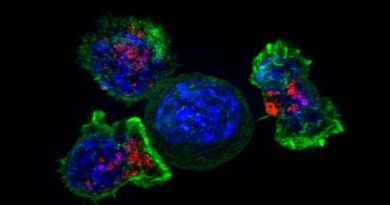

En su sentido más general, el cáncer es definido como una enfermedad en la que algunas células del cuerpo se multiplican de manera descontrolada y se esparcen por diferentes zonas del cuerpo. Aunque ese proceso de multiplicación es normal entre las células que se mueren y son reemplazadas por otras jóvenes, cuando aparece el cáncer ese proceso se modifica y forma nuevas unidades cuando no debería.

Esa creación desorganizada provoca tumores que pueden ser malignos e impactan directamente en la salud del paciente, aunque hay tipos de cáncer, como la leucemia, que no necesariamente se presentan en forma de masas.